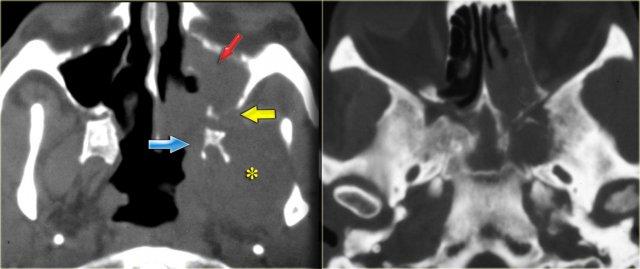

Bên trái là hình ảnh MRI tương ứng.

Trước tiên hãy nghiên cứu các hình ảnh, sau đó tiếp tục đọc.

Các phát hiện bao gồm:

- Dịch trong xoang bướm phải (mũi tên đỏ).

- Mô giảm tín hiệu trong xoang bướm trái (mũi tên vàng).

- Lan rộng dọc theo bờ màng cứng của hố sọ giữa (mũi tên xanh dương).

- Lan rộng vào khoang gò má-cơ nhai trái (mũi tên vàng lớn).

- Sau tiêm thuốc tương phản từ, không có ngấm thuốc dạng đặc của mô trong khoang bướm.

Tiếp tục xem hình ảnh mặt phẳng coronal.

Hình ảnh mặt phẳng coronal của cùng bệnh nhân: T1 trước và sau tiêm thuốc tương phản từ.

Hình ảnh bình thường của hang Meckel bên phải; mô trong hang Meckel bên trái lan rộng vào xoang hang (mũi tên xanh dương).

Mũi tên đỏ chỉ vào bờ màng cứng của xoang hang: có ngấm thuốc ở cả hai mặt của màng cứng.

Bệnh lý bao quanh thùy thái dương (mũi tên xanh lá) và lan xuống dưới qua lỗ bầu dục (mũi tên vàng) vào khoang cơ nhai.

Dấu hoa thị chỉ mô bình thường không ngấm thuốc trong khoang cơ nhai.

Bệnh nhân này bị u lympho.

Chín trong mười trường hợp, bệnh nhân suy giảm miễn dịch sẽ bị nhiễm nấm, một trong mười trường hợp sẽ là u lympho.

CT và MRI có vai trò bổ sung cho nhau trong trường hợp này, nhưng cuối cùng cần sinh thiết để phân biệt hai chẩn đoán này, vì phương pháp điều trị khác nhau.